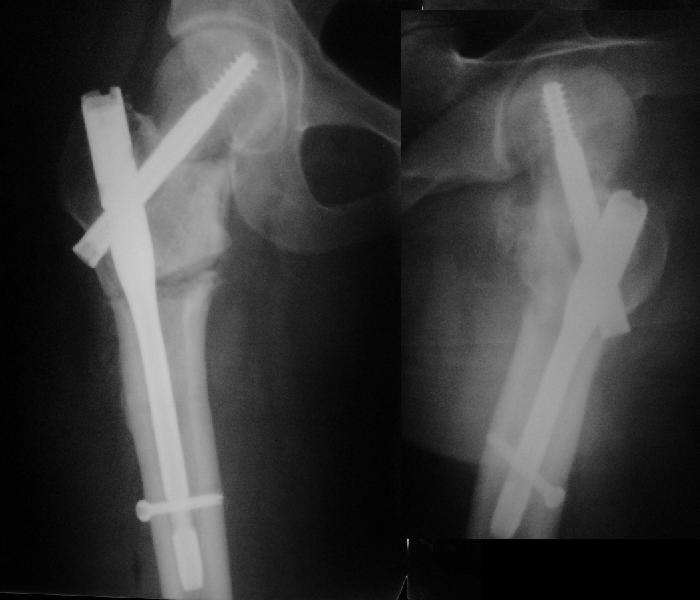

Я бы ограничился вальгизацией без вмешательства в зону перелома шейки. Биология здесь, надо полагать, хорошая, необходимо только улучшить механическую составляющую.

В итоге что-то такое и сделали. Убрали DHS, остеотомия, синтезировали Affixus с небольшой вальгизацией. Снимки в приложении.

Ну, чтож, теперь будем посмотреть).

Интересен результат через 6-12-24-и т.д. месяцев

Похоже удалось провести шеечный винт мимо старого канала, и вальгус, вроде, удался. Только хороший-ли контакт фрагментов в зоне остеотомии? Действительно - жизнь покажет.